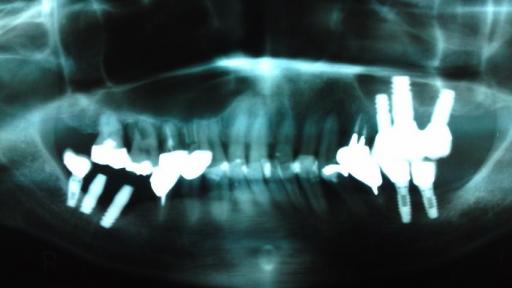

限界に近い ソケットリフト症例 (1)

Before After

最新の骨補填剤 「ダイナブラスト」を利用した ソケットリフト ケース

患者様は、 術後 全く痛みが無かった為 早く下の奥歯もやりたいとおっしゃっています。